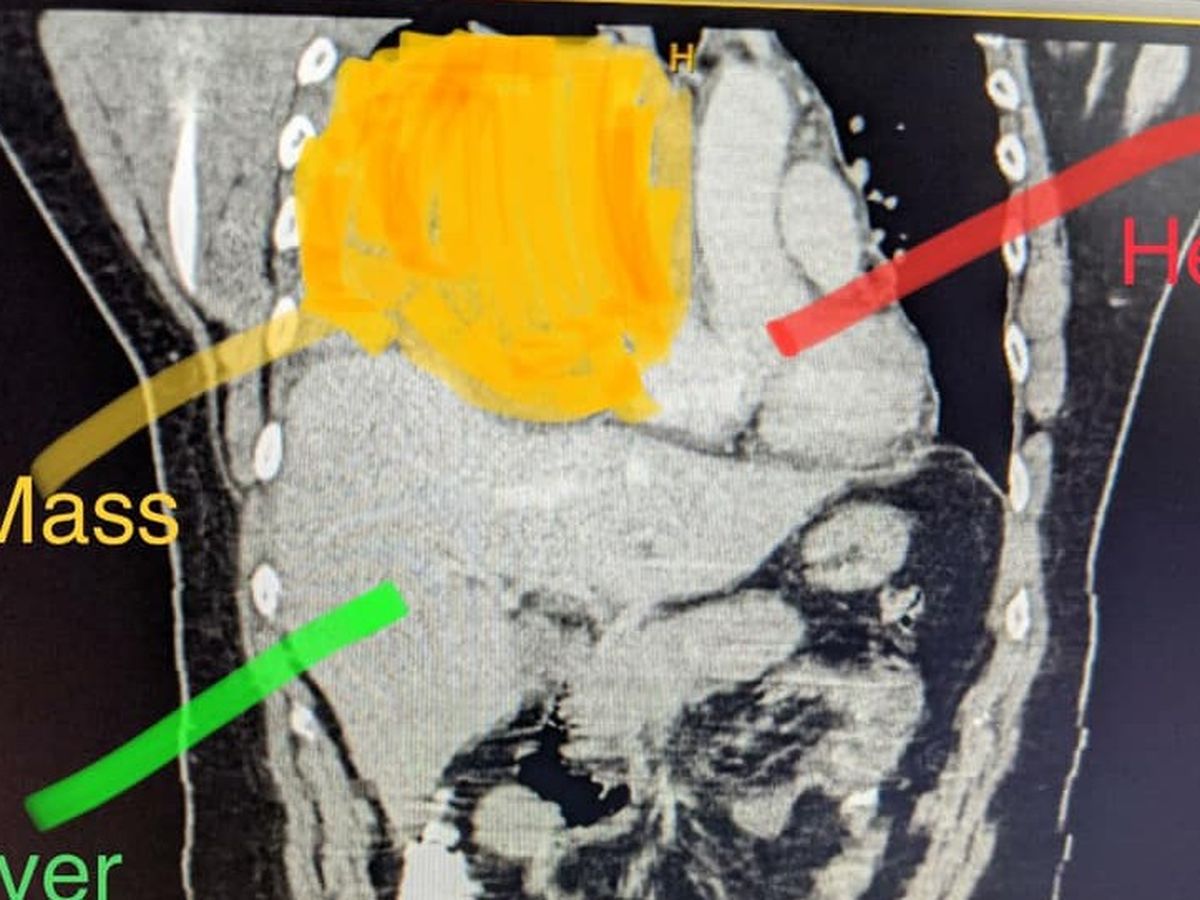

Out of the blue I was diagnosed with pneumonia and a couple weeks later with a mass in my chest- which turned out to be a Germ-Cell Tumor of Testicular Cancer

(extremely rare)

The results from the two MRIs they did yesterday came back. The one for my brain is great but the one for my spine does show that there is infiltration on the T3 vertebrae. That means there is a very small tumor in my spine that's the same type as the one that's in my chest.